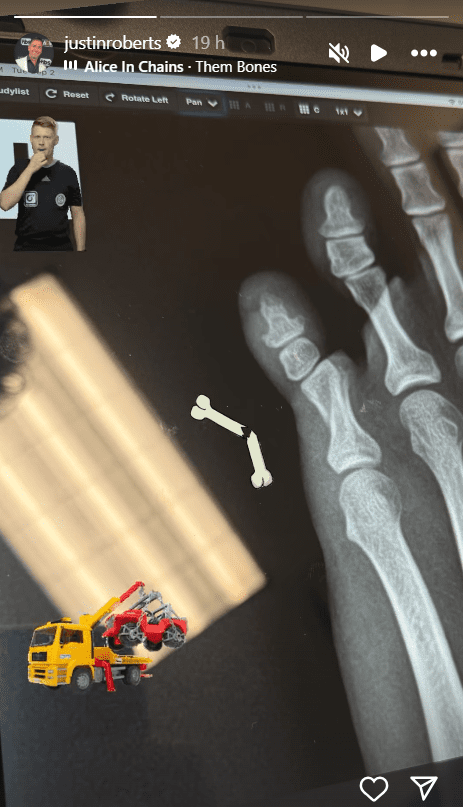

AEW announcer Justin Roberts took to his Instagram story and uploaded a photo of an X-ray, revealing that one of his toes was broken and the graphic image showed the extent of the damage. Roberts still took it in stride as he included a broken bone emoji as well as played Alice in Chains’ “Them Bones” for good measure.